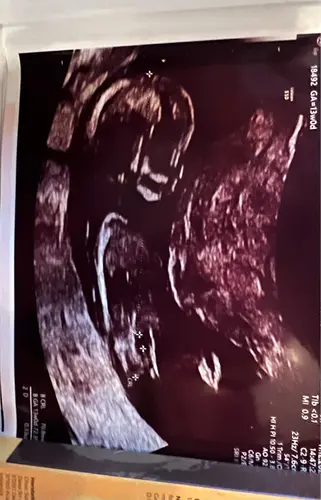

Deze heb ik

Hoeveel weken ben je hier precies? Er staat 11w in je profiel

Ja 11 weken en 3 dagen

Ohh veeeel te vroeg. Tis nu een meisje maar het kan zéker nog jongetje worden als ik naar de foto's kijk. Dus volgende echo weer ff plaatsen dan is het vast duidelijk en met (meer) zekerheid te zeggen.

Potty shot! Wat kan dit zijn? Ze kon het wel zien zei ze! Ben echt benieuwd. Ik deel nog een volledige foto in m’n volgende comment🥹